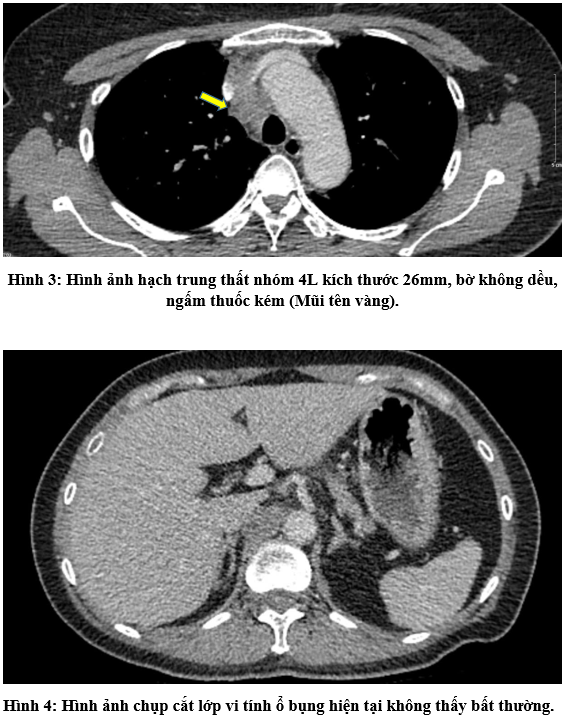

- Chụp cắt lớp vi tính lồng ngực:

- Chụp cắt lớp vi tính ổ bụng: Không phát hiện tổn thương bất thường.